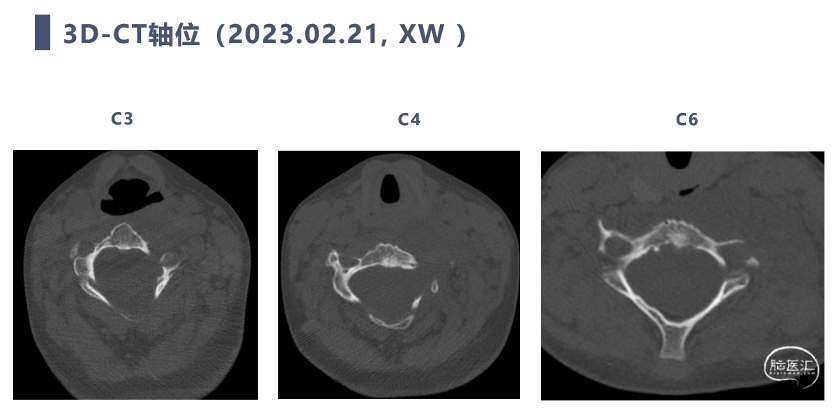

CT

CT显示颈椎椎体最大深度只有8mm,枢椎椎弓根直径3.2mm